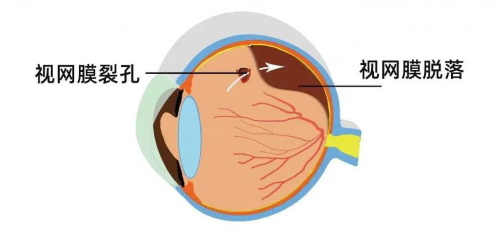

视网膜疾病:视网膜脱离、糖尿病视网膜病变、视网膜静脉阻塞等

对于视网膜脱离患者,她能根据病情选择外路手术或玻璃体切割手术,提高手术成功概率。

实例三:28岁男性,因"右眼外伤后视力丧失"急诊入院。检查发现右眼复杂性视网膜脱离伴玻璃体积血。雷医生急诊为其进行了玻璃体切割联合视网膜复位手术,术后3个月复查,视网膜复位良好,视力修复至0.4。

复杂性视网膜脱离复位术:成功概率高,术后视力修复良好